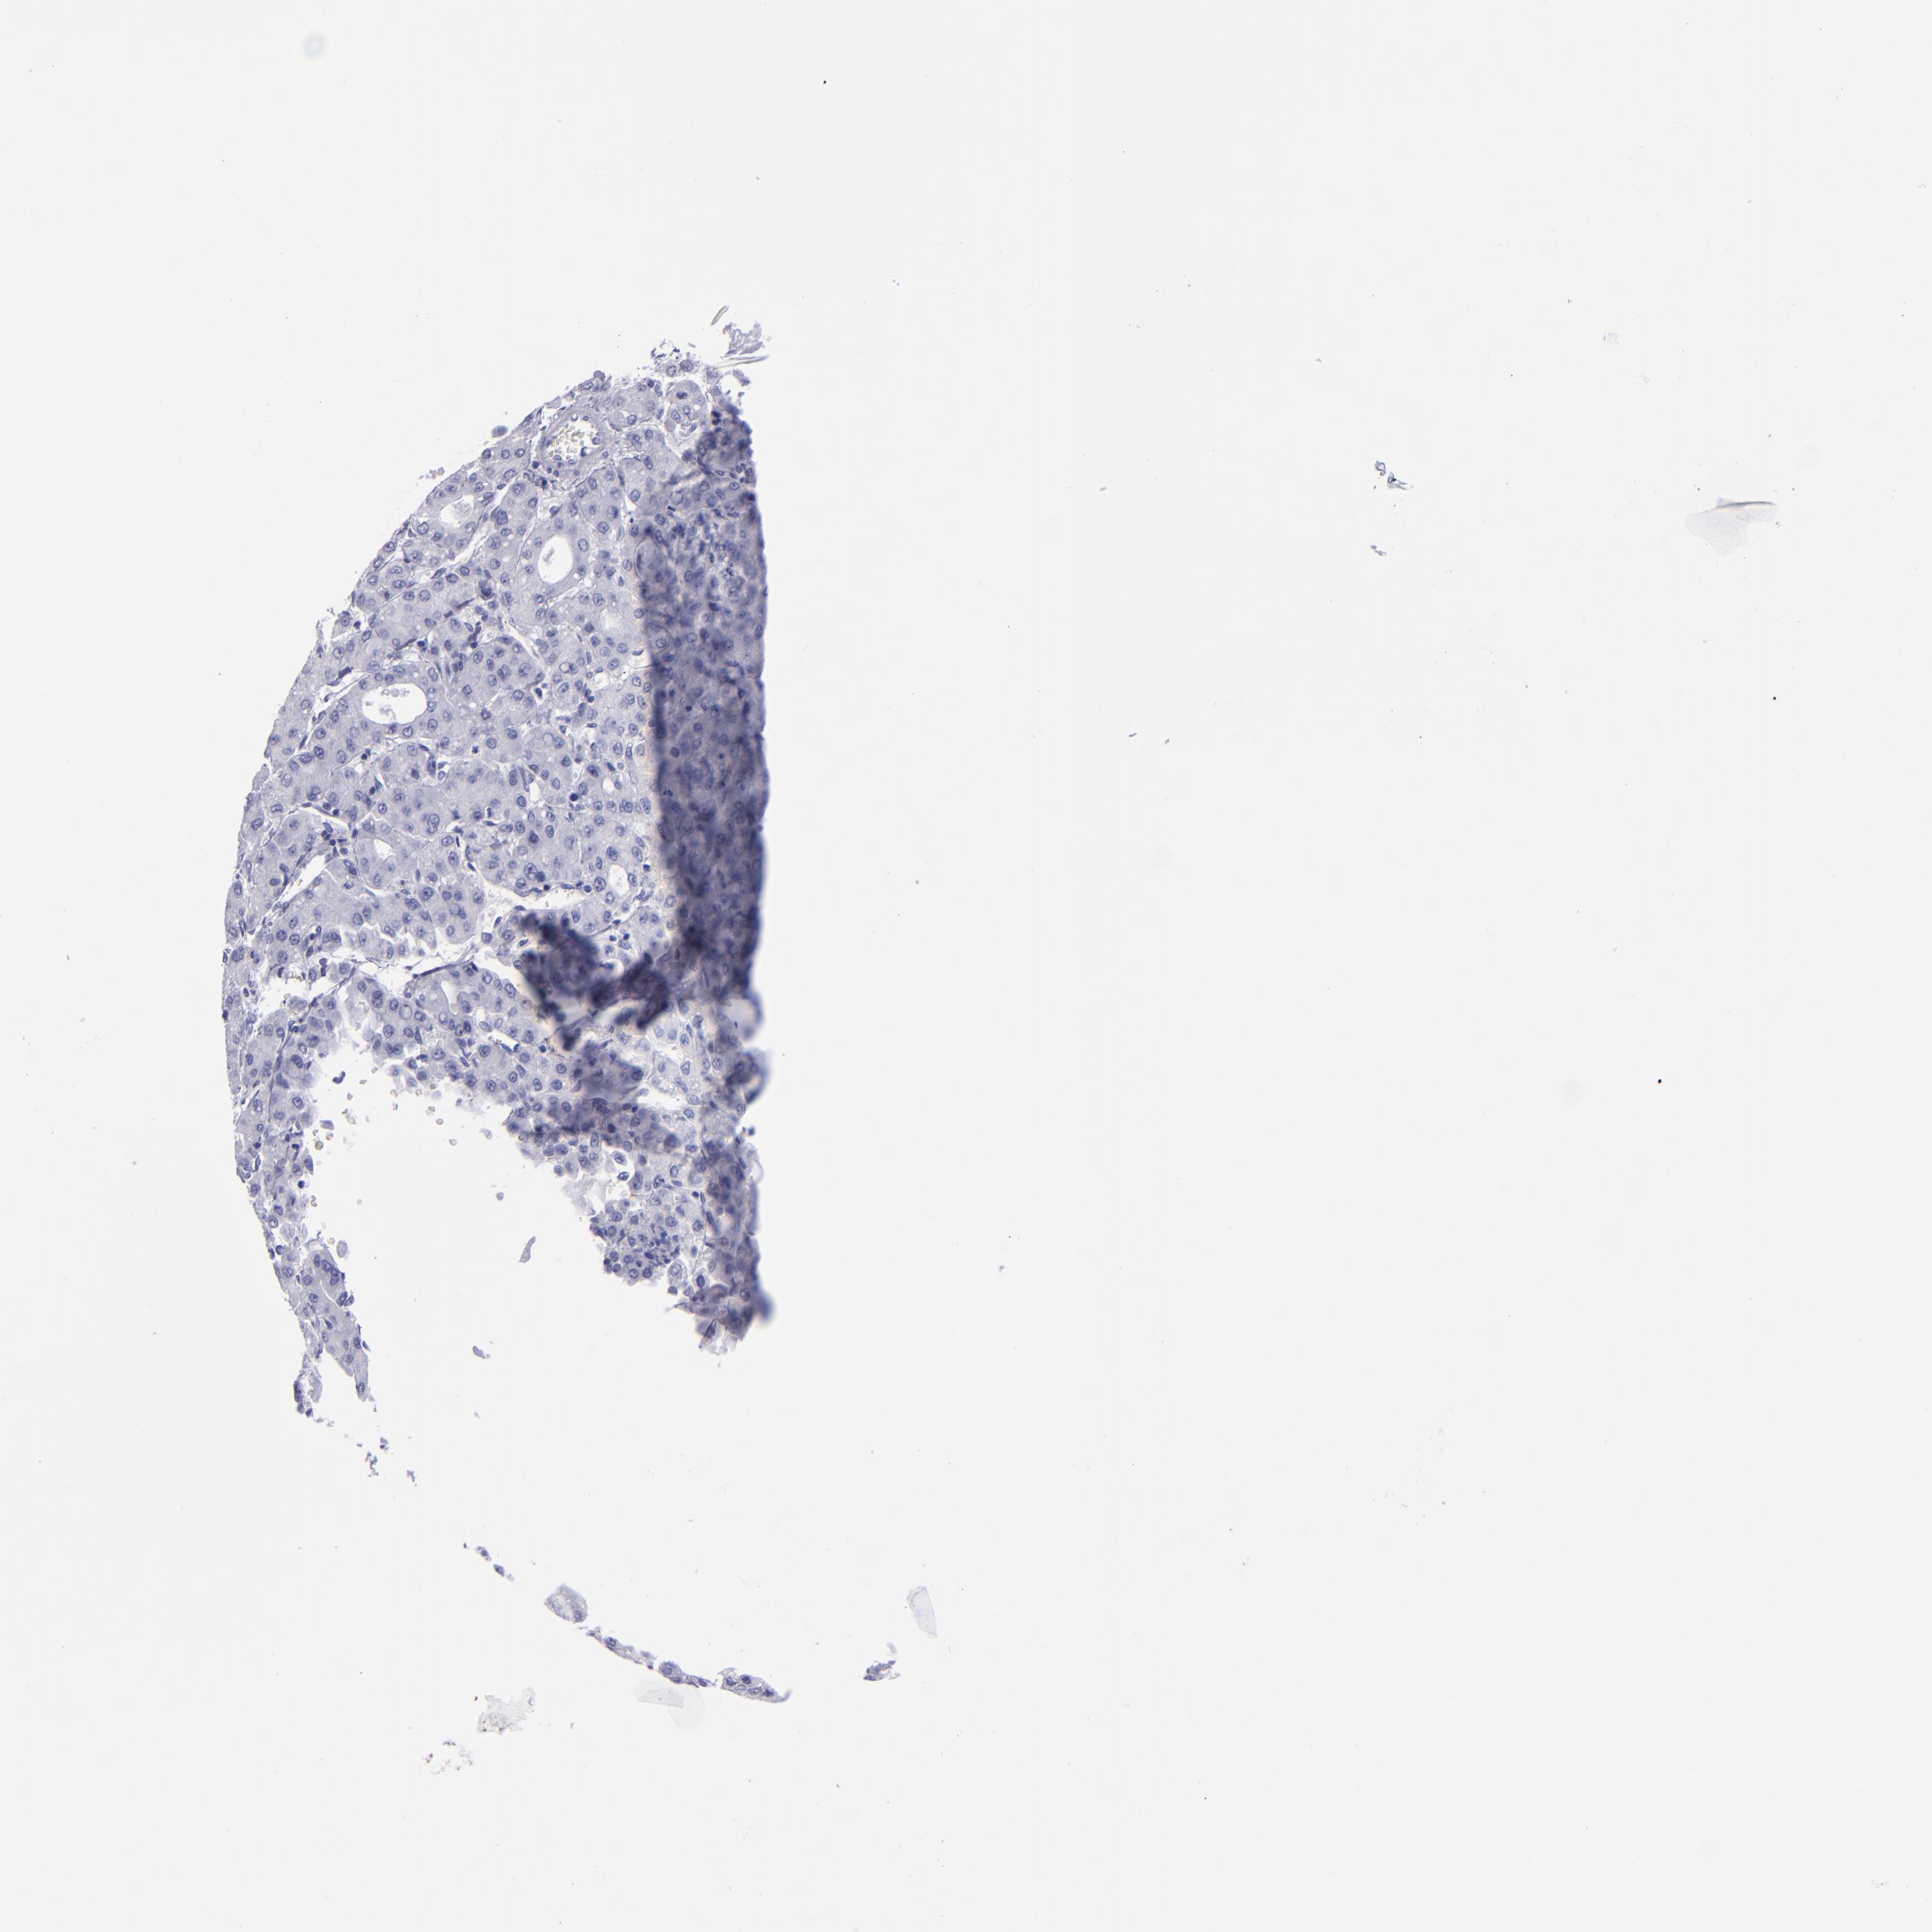

LIVER CANCER - Protein expressioni

A mouse-over function shows sample information and annotation data. Click on an image to view it in a full screen mode. Samples can be filtered based on level of antibody staining by selecting one or several of the following categories: high, medium, low and not detected. The assay and annotation is described here.

Note that samples used for immunohistochemistry by the Human Protein Atlas do not correspond to samples in the TCGA dataset.

Antibody stainingi

Antibody staining in the annotated cell types in the current human tissue is reported as not detected, low, medium, or high, based on conventional immunohistochemistry profiling in selected tissues. This score is based on the combination of the staining intensity and fraction of stained cells.

Each image is clickable and will lead to virtual microscopy that enables deeper exploration of all samples and also displays staining intensity scores, fraction scores and subcellular localization as well as patient and tissue information for each sample.

Antibody HPA022132

Antibody HPA052381

Antibody CAB002493

Antibody CAB025255

Staining

High

Medium

Low

Not detected

Intensity

Strong

Moderate

Weak

Negative

Quantity

>75%

75%-25%

<25%

None

Location

Nuclear

Cytoplasmic/membranous

Cytoplasmic/membranous,nuclear

Cholangiocarcinoma

Carcinoma, Hepatocellular, NOS